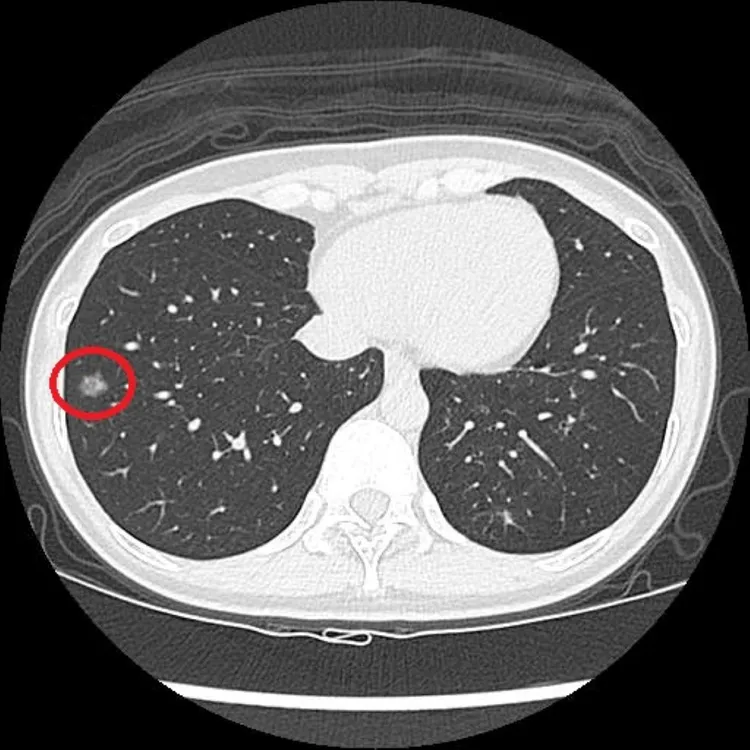

LDCT檢查顯示,陳小姐右側肺部有一1.2公分大的毛玻璃結節。台北慈濟醫院提供